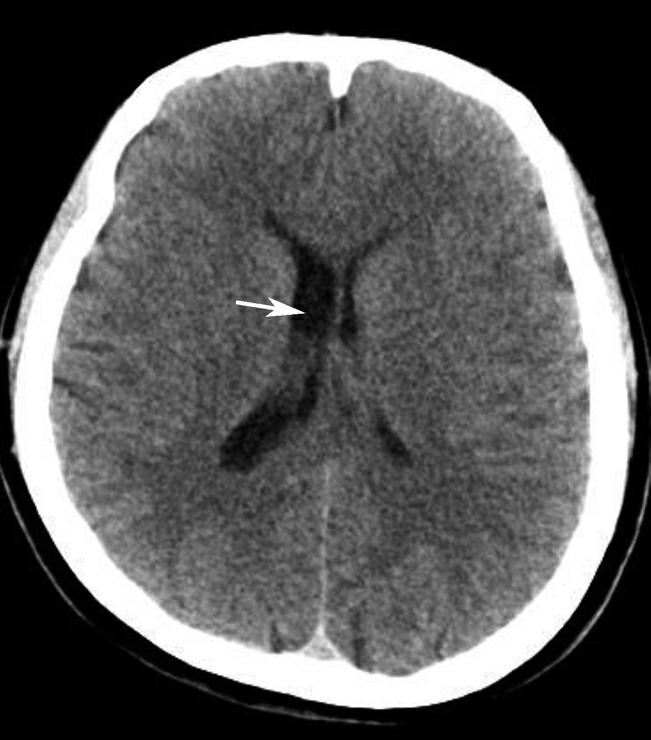

基底节为脑卒中的好发部位,与纹状动脉的解剖特点有关,深穿支动脉的破裂和栓塞可分别引起基底节区的出血和梗死(图1-2-32、图1-2-33)。

图1-2-32 脑出血

A.右侧壳核脑出血,形成高密度血肿(★);B.右侧丘脑出血,呈球形高密度影(箭)

图1-2-33 基底节区脑梗死

A.右侧丘脑梗死,病灶呈圆形低密度影(箭);B.左侧内囊膝部及后肢梗死,呈带状低密度影(箭)